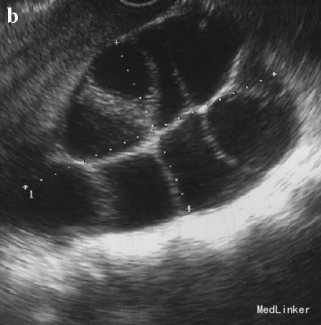

31岁女性,G2,孕10周,因诊断OHSS合并卵巢肿块就诊

hCG 390000 IU/L 超声提示胎盘上有数个囊性肿块,胎儿无胎心 超声还提示双侧卵巢囊性肿块

诊断为OHSS合并葡萄胎 行诊断性刮宫,提示葡萄胎 术后hCG 9830 IU/L OHSS症状愈加明显 患者卵巢增大、出现胸水、腹水,体重增加 术后17天症状缓解 1月后卵巢恢复正常大小 刮宫后20周hCG恢复正常